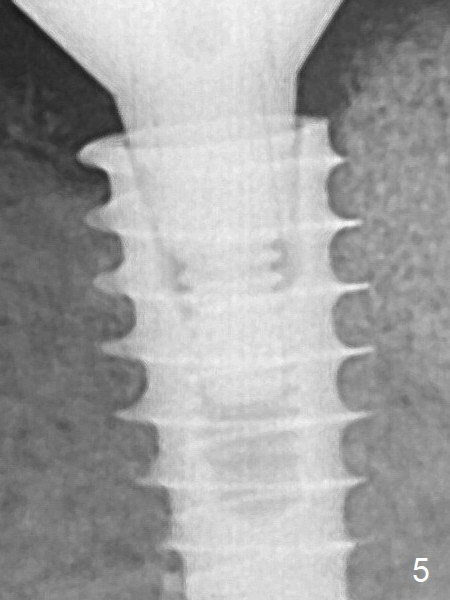

A provisional is fabricated 3 weeks postop.  The provisional and abutment are loose 4 months postop (Fig.5).  After retightening the abutment, impression is taken for final restoration.